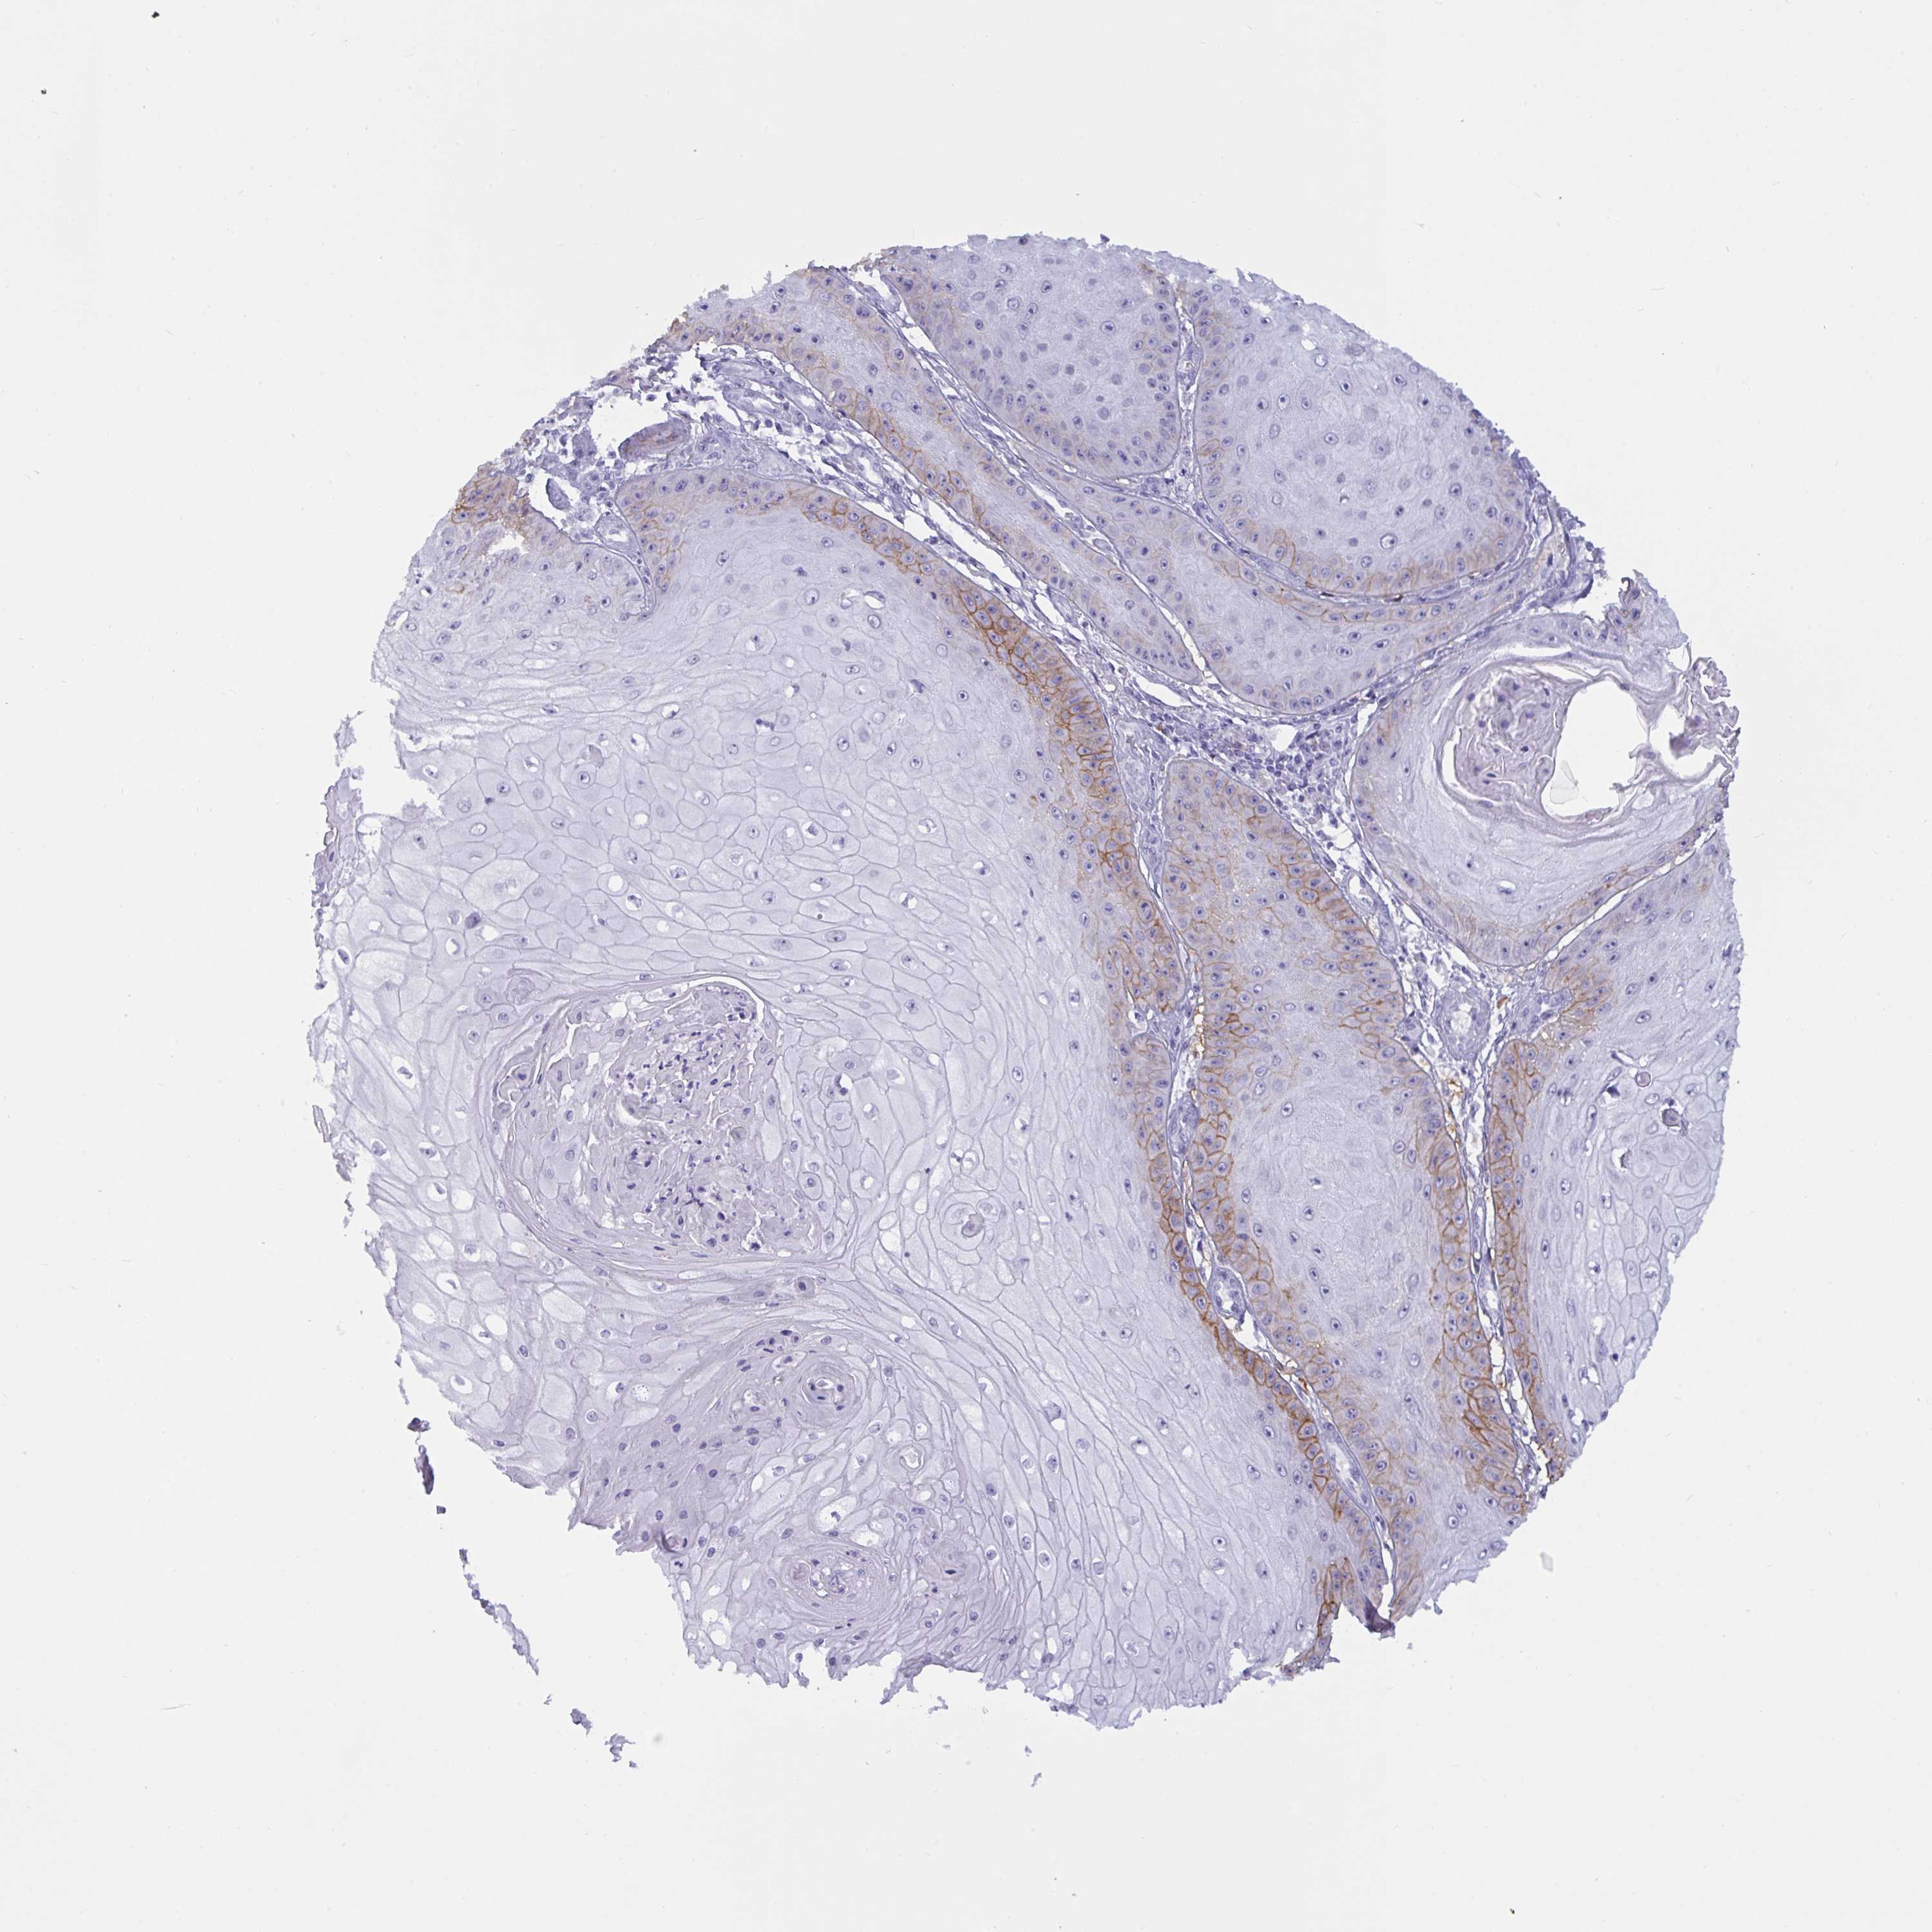

Basal cell and squamous cell cancer

SKIN CANCER - Protein expressioni

A mouse-over function shows sample information and annotation data. Click on an image to view it in a full screen mode. Samples can be filtered based on level of antibody staining by selecting one or several of the following categories: high, medium, low and not detected. The assay and annotation is described here.

Each image is clickable and will lead to virtual microscopy that enables deeper exploration of all samples and also displays staining intensity scores, fraction scores and subcellular localization as well as patient and tissue information for each sample.

Antibody HPA058494

Squamous cell carcinoma, NOS